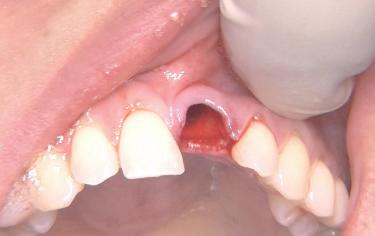

Situation avant la prise d’empreinte en sept. 2009

• Etude de la prothèse sur implants (provisoire, immédiate et définitive).

Situation pré-opératoire 09/2018 09/2018

Contrôle à 10 ans en septembre 2018.